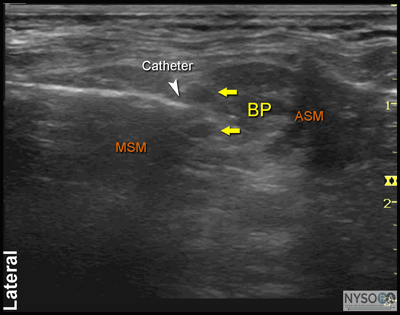

Figure 9: Continuous brachial plexus block. Needle is inserted in the interscalene space using an in-plane approach. Please note that for better demonstration, sterile drapes are not used in the model in this figure. ![]() Figure 10: An ultrasound image demonstrating needle and catheter (white arrow) inserted in the interscalene space between the anterior (ASM) and middle (MSM) scalene muscles. BP, brachial plexus.

Proper placement of the needle can also be confirmed by obtaining a motor response of the deltoid muscle, arm, or forearm (0.5 mA, 0.1 msec) at which point 4 to 5 mL of local anesthetic can be injected. This small dose of local anesthetic serves to assure adequate distribution of the local anesthetic as well as to make the advancement of the catheter more comfortable to the patient. This first phase of the procedure does not significantly differ from the single-injection technique. The second phase of the procedure involves maintaining the needle in the proper position and inserting the catheter 2 to 3 cm into the interscalene space in the vicinity of the brachial plexus (Figure 10). Insertion of the catheter can be accomplished by a single operator or with a helper. Proper location of the catheter can be determined either by visualizing the course of the catheter or by an injection of the local anesthetic through the catheter. When this proves difficult, alternatively, a small amount of air (1 mL) can be injected to confirm the catheter tip location. There is no agreement on what constitutes the ideal catheter securing system. The catheter is secured by either taping to the skin or tunneling. Some clinicians prefer one over the other. However, the decision about which method to use could be based on the patient's age, duration of the catheter therapy, and anatomy. Tunneling could be preferred in older patients with obesity or mobile skin over the neck and when longer duration of catheter infusion is expected. Two main disadvantages of tunneling are the risk of catheter dislodgment during the tunneling and the potential for scar formation. Fortunately, a number of catheter-securing devices are available to help stabilize the catheter.